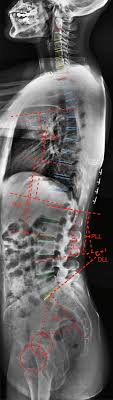

The ligament around this joint relaxes during pregnancy. Knowledge of normal pelvic anatomy on mri is critical for proper interpretation, in particular the standard visceral organ appearances, commonly encountered variants, and pathology mimics. The sagittal (longitudinal) image of the female pelvis shows anatomical structures. The nerve supply to most of the muscles in this compartment is the obturator nerve, which arises from the lumbar plexus from. Human spine and pelvis anatomy model.

Knowledge of normal pelvic anatomy on mri is critical for proper interpretation, in particular the standard visceral organ appearances, commonly encountered variants, and pathology mimics.